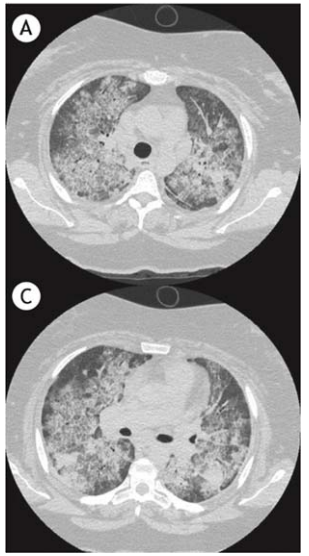

Um homem de 44 anos de idade, portador de IC há dez anos, em uso regular de furosemida (40 mg por dia), espironolactona (25 mg por dia), losartana (50 mg por dia) e amiodarona (400 mg por dia), em razão de episódio de taquicardia ventricular sustentada há três anos, ao exame físico, mostrava-se em estado geral regular, com tosse não produtiva, dispneia e ausência de febre, FR de 18 irpm, sat. de O2 de 97% em ar ambiente, FC de 54 bpm e PA de 130 x 90 mmHg, bilateralmente. Foi iniciado um tratamento para insuficiência cardíaca descompensada e introduziu-se ceftriaxone para a infecção pulmonar. Não houve melhora com essas condutas. Realizou-se um estudo tomográfico (mostrado a seguir) e uma biópsia transbrônquica, que mostrou pneumonia intersticial crônica não específica, com moderado infiltrado inflamatório mononuclear no septo alveolar e abundante número de macrófagos nos espaços alveolares.

Com base nesse caso hipotético, assinale a alternativa que apresenta o diagnóstico mais provável.